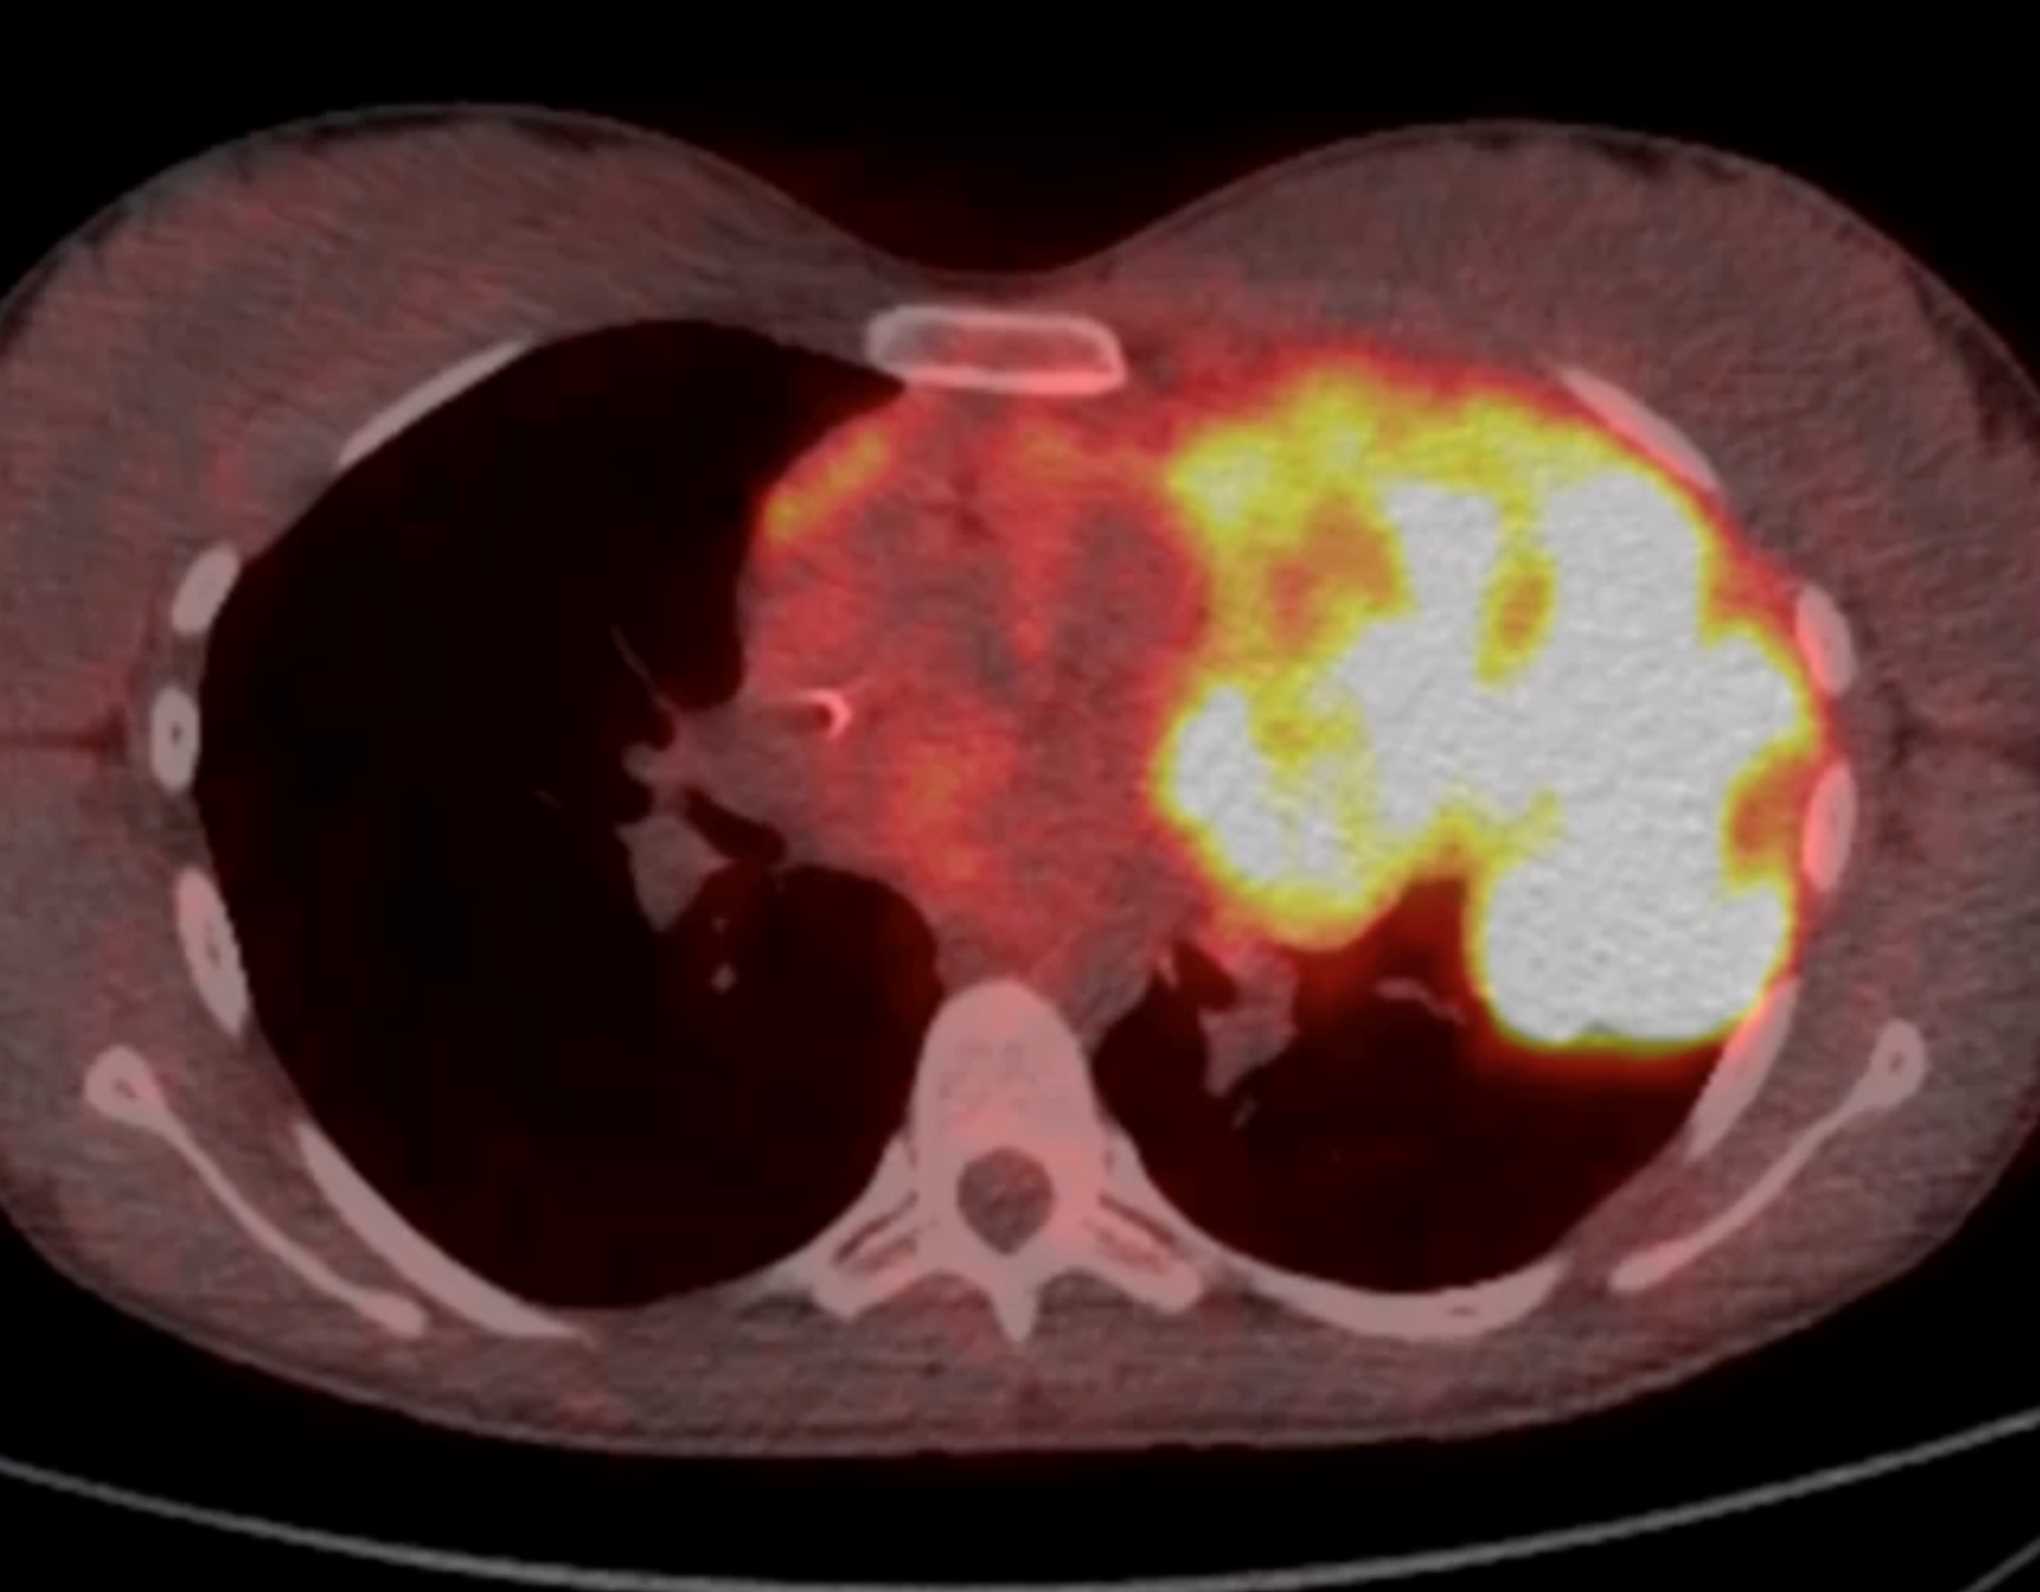

Subtle Adenocarcinoma Pancreas